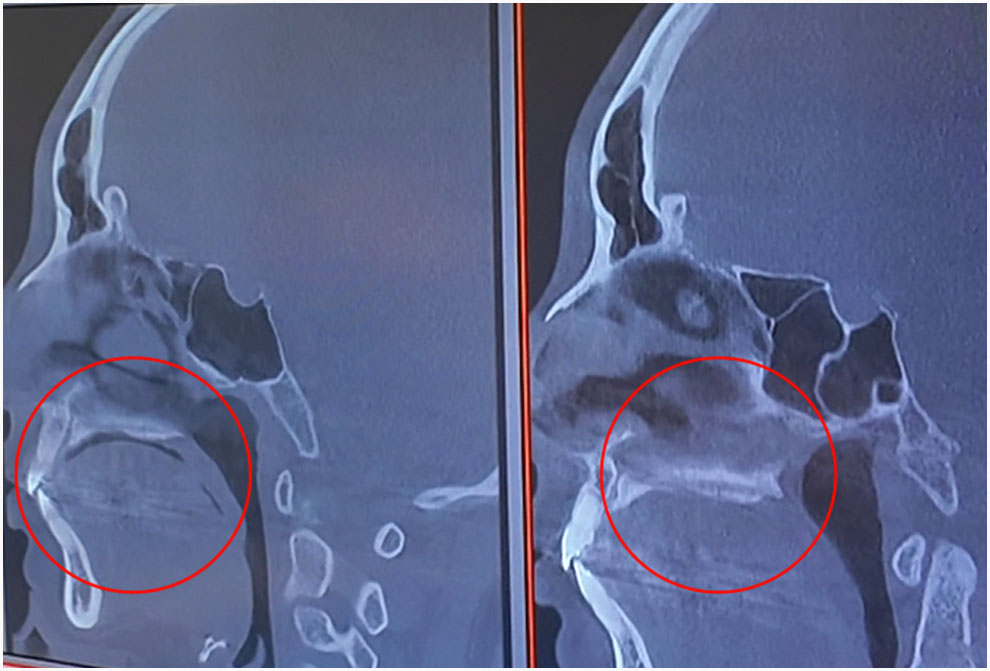

정상적인 턱관절 상태라면 둥그런 형태를 보이는데 문제가 있다면 뼈가 닳아 뾰족해지면서 턱이 틀어지게 됩니다.

정상적인 상태의 턱관절이라면 위 CT 사진처럼 옆면에서 봤을 때 겹쳐 안 보여야 하는 양쪽인데 턱 라인이 보이는 것입니다.

3D CT로 촬영한 단면이며 내려간 혀 위치가 위로 올라가게 되었습니다.

엑스레이로 보면 막힌 코가 뚫리기도 합니다.